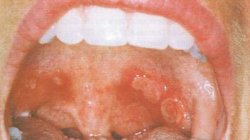

Οι βλάβες του στόματος υποτροπιάζουν στα χείλη, τη γλώσσα, τον παρειακό βλεννογόνο, τη μαλθακή και σκληρή υπερώα, τις αμυγδαλές, ακόμη και στο φάρυγγα ή τη ρινική κοιλότητα. Οι βλάβες είναι μονήρεις ή πολλαπλές, διαμέτρου 2 ως 10 mm ή και μεγαλύτερης, σαφώς περιγεγραμμένες, με ρυπαρή γκριζωπή βάση και περιφερική ζωηρά ερυθρή άλω. Άλλοι ασθενείς εμφανίζουν βαθιά έλκη που καταλείπουν ουλές που μοιάζουν με τις προκαλούμενες από τα μείζονα αφθώδη έλκη του Sutton. Οι βλάβες είναι τόσο επώδυνες που μπορεί η λήψη τροφής να καταστεί δύσκολη. Στις περισσότερες περιπτώσεις διαπιστώνεται έντονη δυσοσμία στόματος.